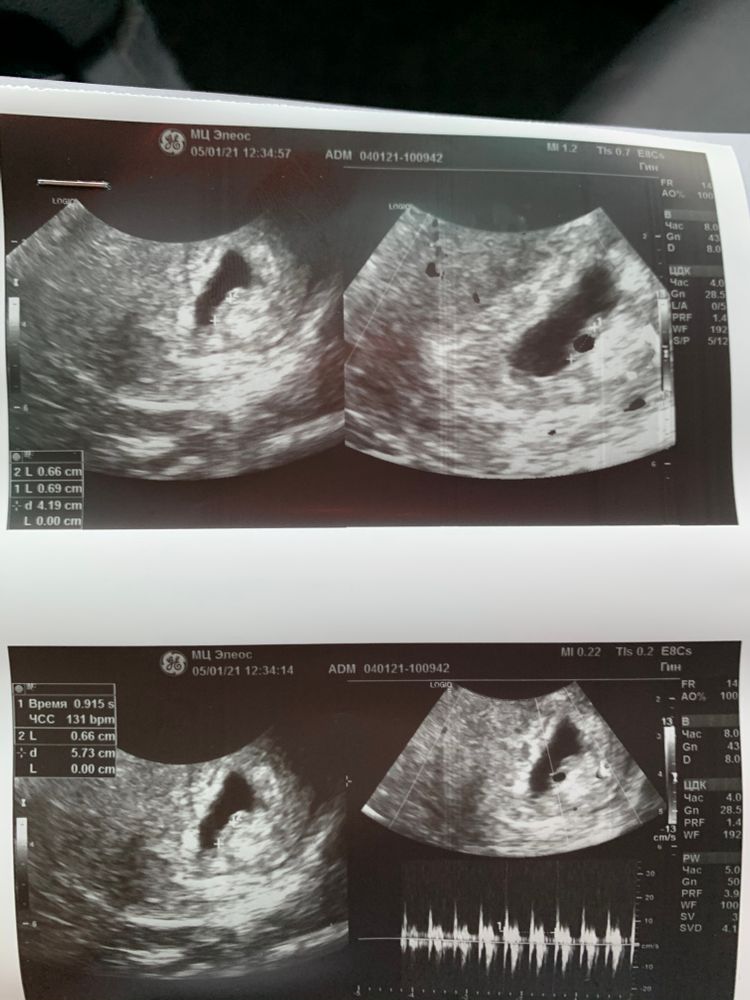

Может кто умелец по методу Рамзи определить пол?)

Всё ещё зависит, как делали узи: по животу или трансвагинально. И если справа, то девочка, слева -мальчик, но быаает и спорно.

Светлана Никиткова, оба узи трансвагинальные

Метод этот не даёт 100% гарантии. Но если на первых фото делали УЗИ трансвагинально, то, похоже, девочка.

Метод определения пола Рамзи, вроде бы, актуален до 7 недель что ли. На втором, как понимаю, уже позже. Знаю здесь девочек, у которых не совпадало.

Юлия Sonnце, я почитала по нему, с 6 недели можно смотреть, а срок до не видела. В 12 недель уже на узи видео будет скорее всего, поэтому в нем просто смысла не остаётся)

Да, в 12 недель опытный врач с хорошим современным аппаратом скажет без сомнений, хоть малыши на этом сроке очень похожи, отличаются наклоном полового бугорка. И вот если у узиста уже глаз намётан, то определит без труда. Про Рамзи здесь читала, что до 7 или 8 недель по нему можно "погадать".